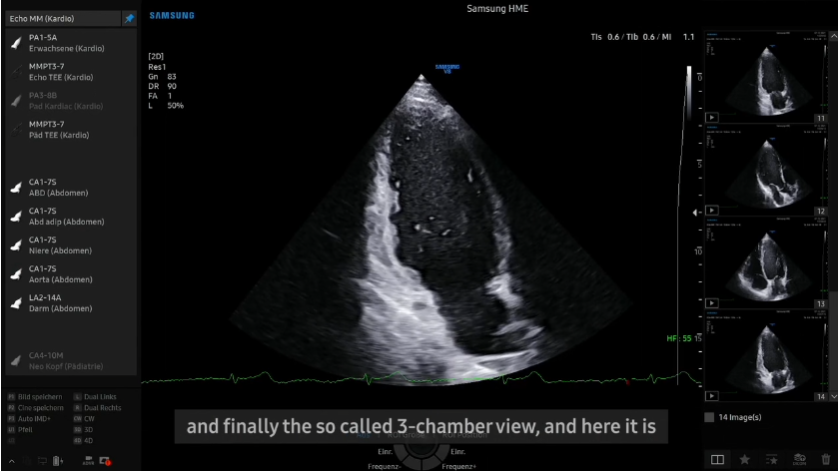

Cardiovascular Case with V8 by Dr. Julia Aland